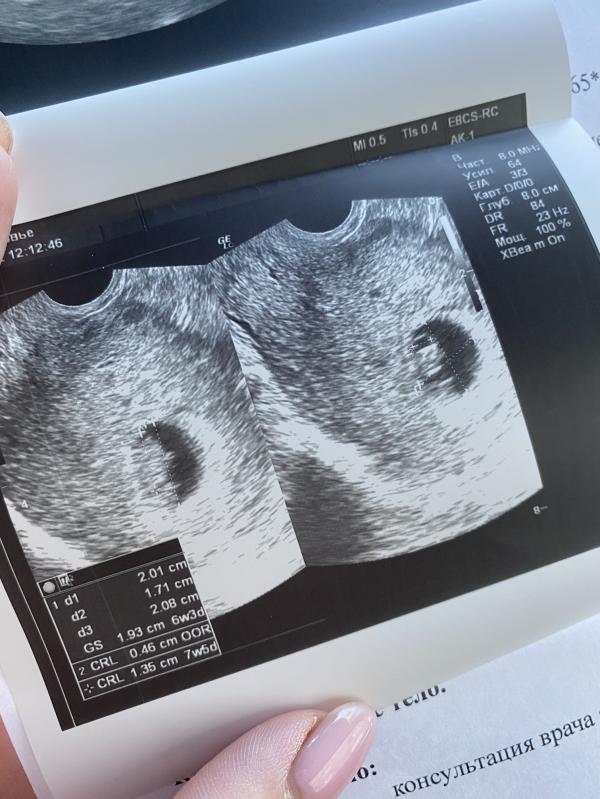

Креветочка растёт 🙏🏽❣️